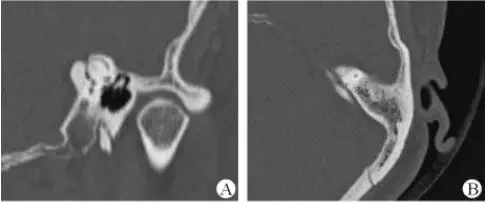

1、上半規(guī)管裂綜合征

內(nèi)耳結(jié)構(gòu)非常微妙。即使是內(nèi)耳中大頭針樣的孔洞也能造成平衡失調(diào)。患者常常不敢進(jìn)行如走路或轉(zhuǎn)頭的日常活動(dòng)。此罕見疾病,醫(yī)學(xué)專家預(yù)估至少影響著人口的1%。可造成惡心,眩暈以及對(duì)噪聲極高的敏感性。病人還常常抱怨他們能聽到血管跳動(dòng)的聲音。其中一位患者曾告訴耳科專家,他都能聽到自己轉(zhuǎn)動(dòng)眼睛的聲音。

診斷及治療

醫(yī)生若懷疑此病將會(huì)安排內(nèi)耳CT掃描。在大多數(shù)案例中,一旦此病被耳鼻喉科醫(yī)生或其它聽力健康專家確診,則可實(shí)行手術(shù)治療。外科手術(shù)風(fēng)險(xiǎn)包含聽力損失以及神經(jīng)損傷;重建及復(fù)原需內(nèi)耳的治療以及大腦的重塑。

2、膽脂瘤

另一個(gè)不常見的疾病叫膽脂瘤,發(fā)病率為1/10000,這個(gè)“腫瘤”在內(nèi)耳中逐漸生長(zhǎng)。盡管不是惡性的,但也能導(dǎo)致永久性的聽力損失以及其它嚴(yán)重的疾病,比如腦膜炎。癥狀是有臭味的耵聹以及聽力損失。